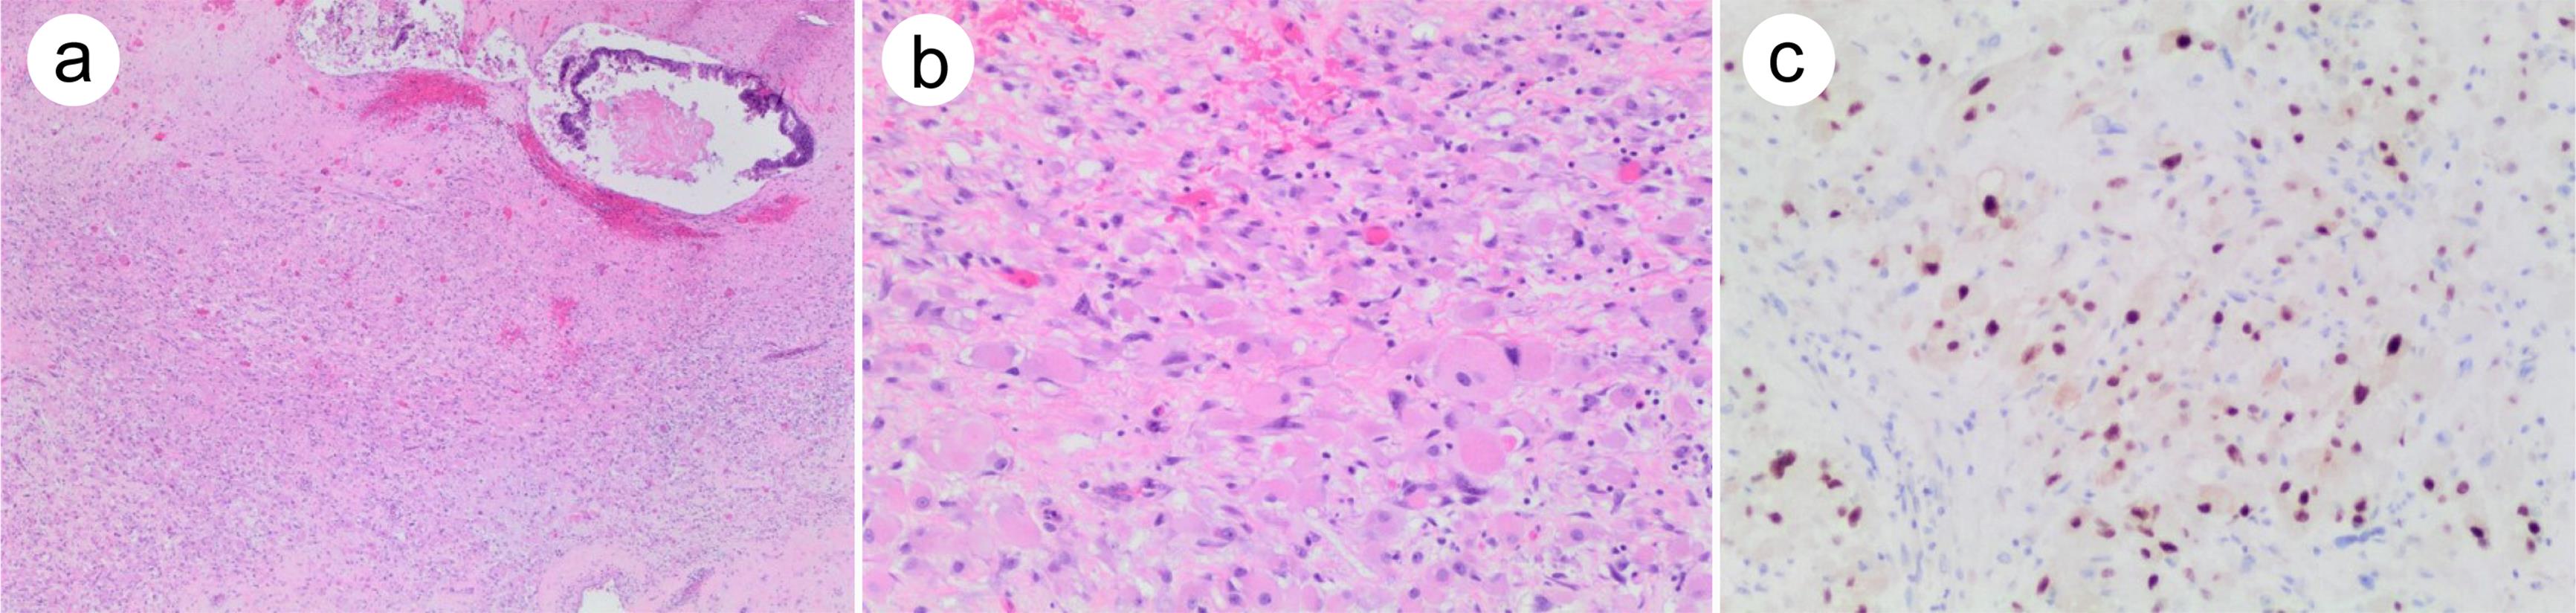

As the most common type of SM, sarcoma has various forms of differentiation, including rhabdomyosarcoma, myxofibrosarcoma, angiosarcoma, and spindle cell tumors, among which rhabdomyosarcoma is the most frequently reported.12 Rhabdomyosarcomas contain rhabdomyoblasts at various stages of myogenesis (Fig. 1a). Well-differentiated rhabdomyoblasts are often elongated with abundant eosinophilic cytoplasm; while the less-differentiated primitive rhabdomyoblasts are round or elliptical cells, with scant cytoplasm in a sheet-like growth pattern (Fig. 1b). Generally, sarcomatous cells show eccentric atypical nuclei and prominent nucleoli with a high mitotic activity.

Fig. 1  Rhabdomyosarcoma arising from testicular teratoma.

(a) Overgrowth of round cells with eosinophilic cytoplasm in a sheet-like growth pattern. Note the residual teratomatous (glandular) component in the right upper corner. (b) High-power view of the tumor showing medium-to-large round cells with eosinophilic cytoplasm, eccentric atypical nuclei, and prominent nucleoli. (c) The tumor cells are strongly positive for myogenin.

The application of immunohistochemistry is often required for diagnosing SM in the testis and metastases. The positive staining of spalt-like transcription factor 4 suggests a germ cell origin, especially with a history of GCTs.14,17 The strong expression of desmin, myogenin (Fig. 1c), and myoblast determination protein 1 can confirm the diagnosis of rhabdomyosarcoma in a GCT.12,18–20 Angiosarcomas are characterized by the expression of CD31, CD34, and ERG, and leiomyosarcoma is positive for smooth muscle actin, desmin, and caldesmon.16 Some SMs exhibit a proliferation of high-grade spindle cells with severe nuclear atypia, which may be focally immunoreactive for spalt-like transcription factor 4 but do not show any specific histological differentiation after comprehensive immunohistochemical analysis. Those SMs are considered high-grade unclassified sarcoma.